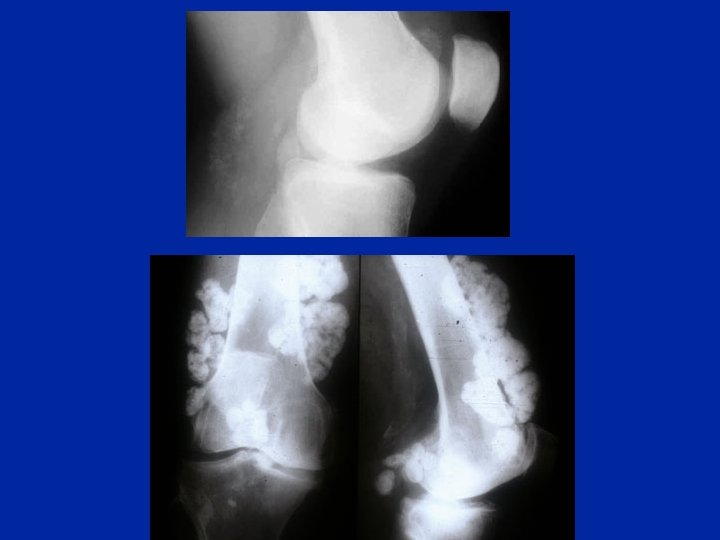

En marge de la gonarthrose Gonarthrose et ostéochondromatose

Ostéochondromatose synoviale

Chondrocalcinose